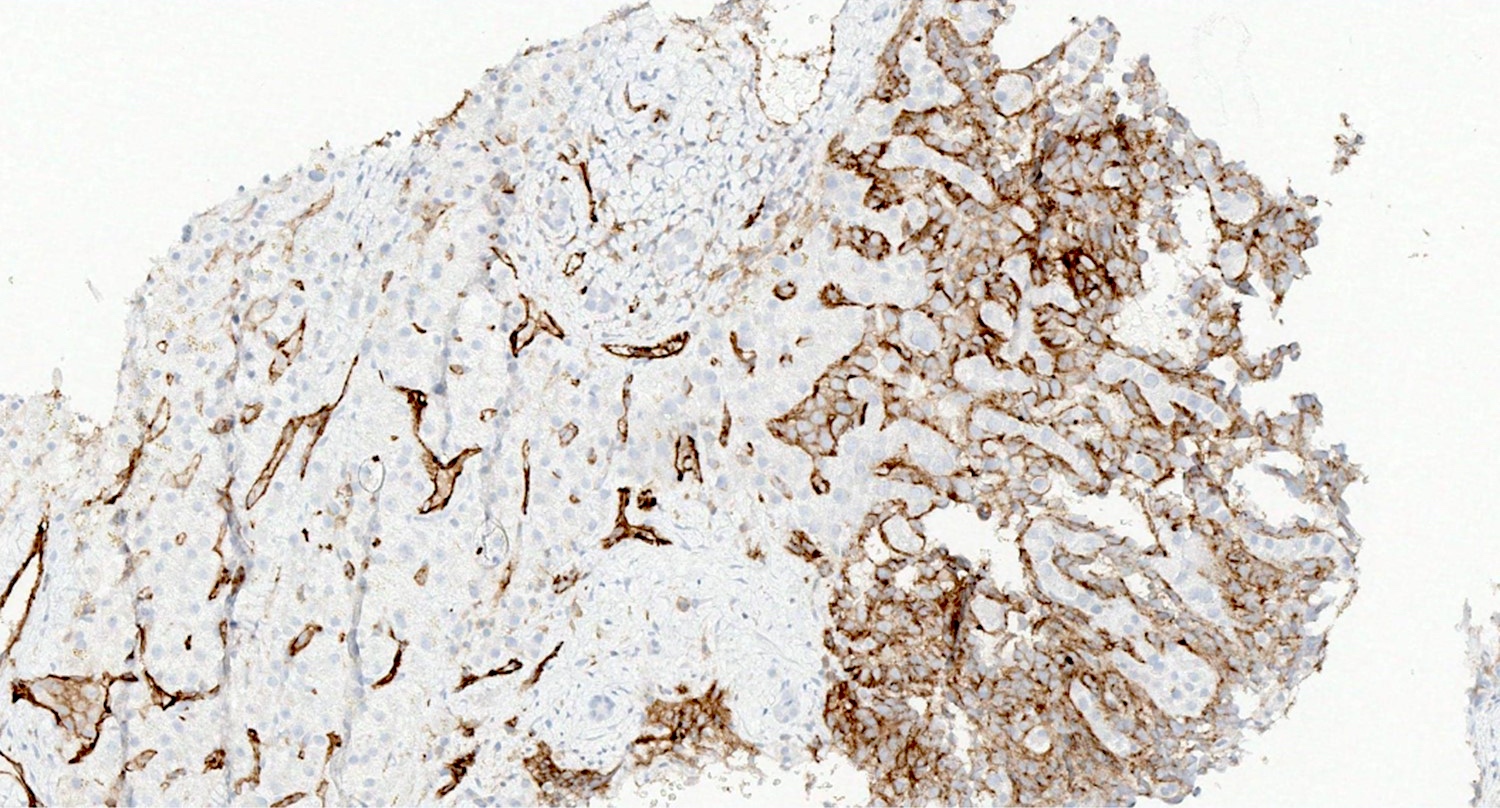

Positive stains

- ERG (nuclear)

- CD31 (membranous)

- CD34 (variable ~50%)

- Factor VIII

- VEGF (Sci Rep 2021;11:9362)

- FLI1

- Ulex europaeus agglutinin I (UEA1) (Histopathology 1986;10:1153)

- D2-40 (podoplanin)

A 55 year old man presents with abdominal pain, weight loss and hepatomegaly. Laboratory studies reveal elevated liver enzymes but normal alpha fetoprotein levels. A liver core needle biopsy is performed. ERG immunohistochemistry is shown in the second image above. What is the most likely diagnosis?

E. Liver angiosarcoma. The histopathology shows nests and sheets of highly atypical neoplastic cells with hyperchromatic and pleomorphic nuclei, which are highlighted by ERG immunohistochemistry in the second image above. This makes liver angiosarcoma the most likely diagnosis.